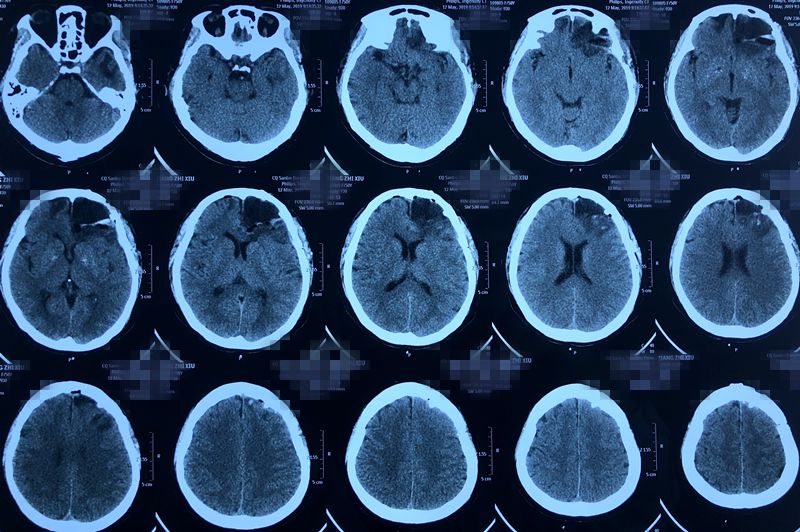

术后复查头颅CT,显示病变切除